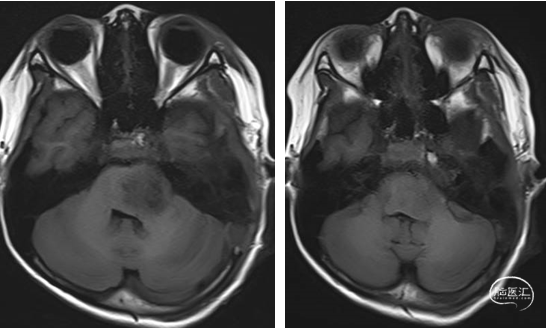

2023年9月13日 MRI T2